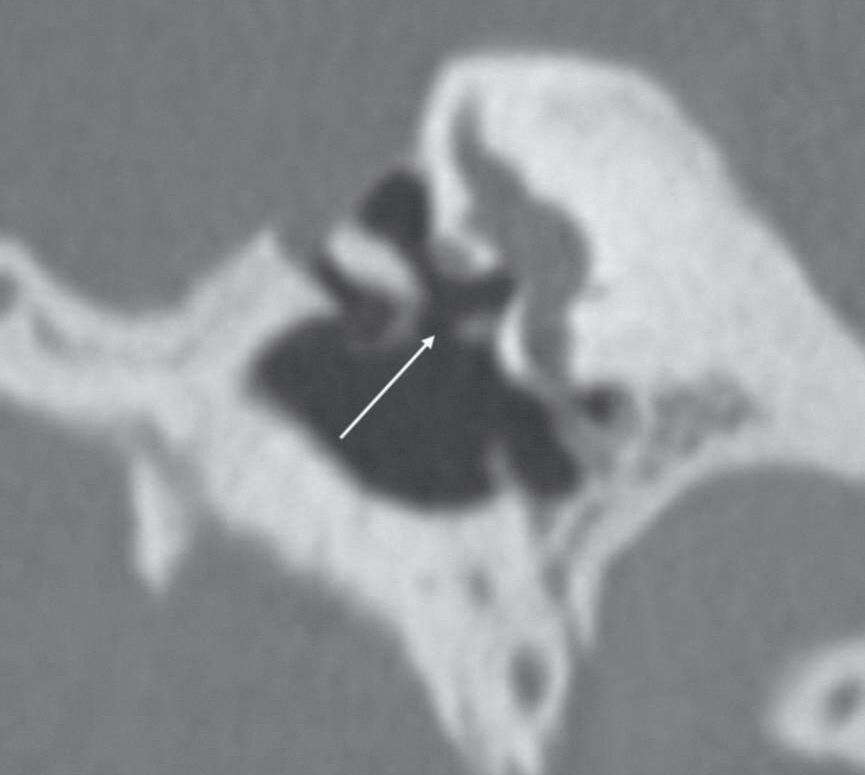

Fig. 1-2. Cadeia ossicular sem e com reformação oblíqua. (a) Tomografia computadorizada de osso temporal, corte coronal, janelamento ósseo, cabeça do martelo sem reformações (seta). (b) Tomografia computadorizada de osso temporal, corte coronal, janelamento ósseo, corpo da bigorna sem reformações (seta). (c) Tomografia computadorizada de osso temporal, corte axial, janelamento ósseo, estribo sem reformação (seta). (d-f) Tomografia computadorizada com reformações coronal e axial oblíquas no eixo da cadeia ossicular, martelo, bigorna e estribo com melhor definição.